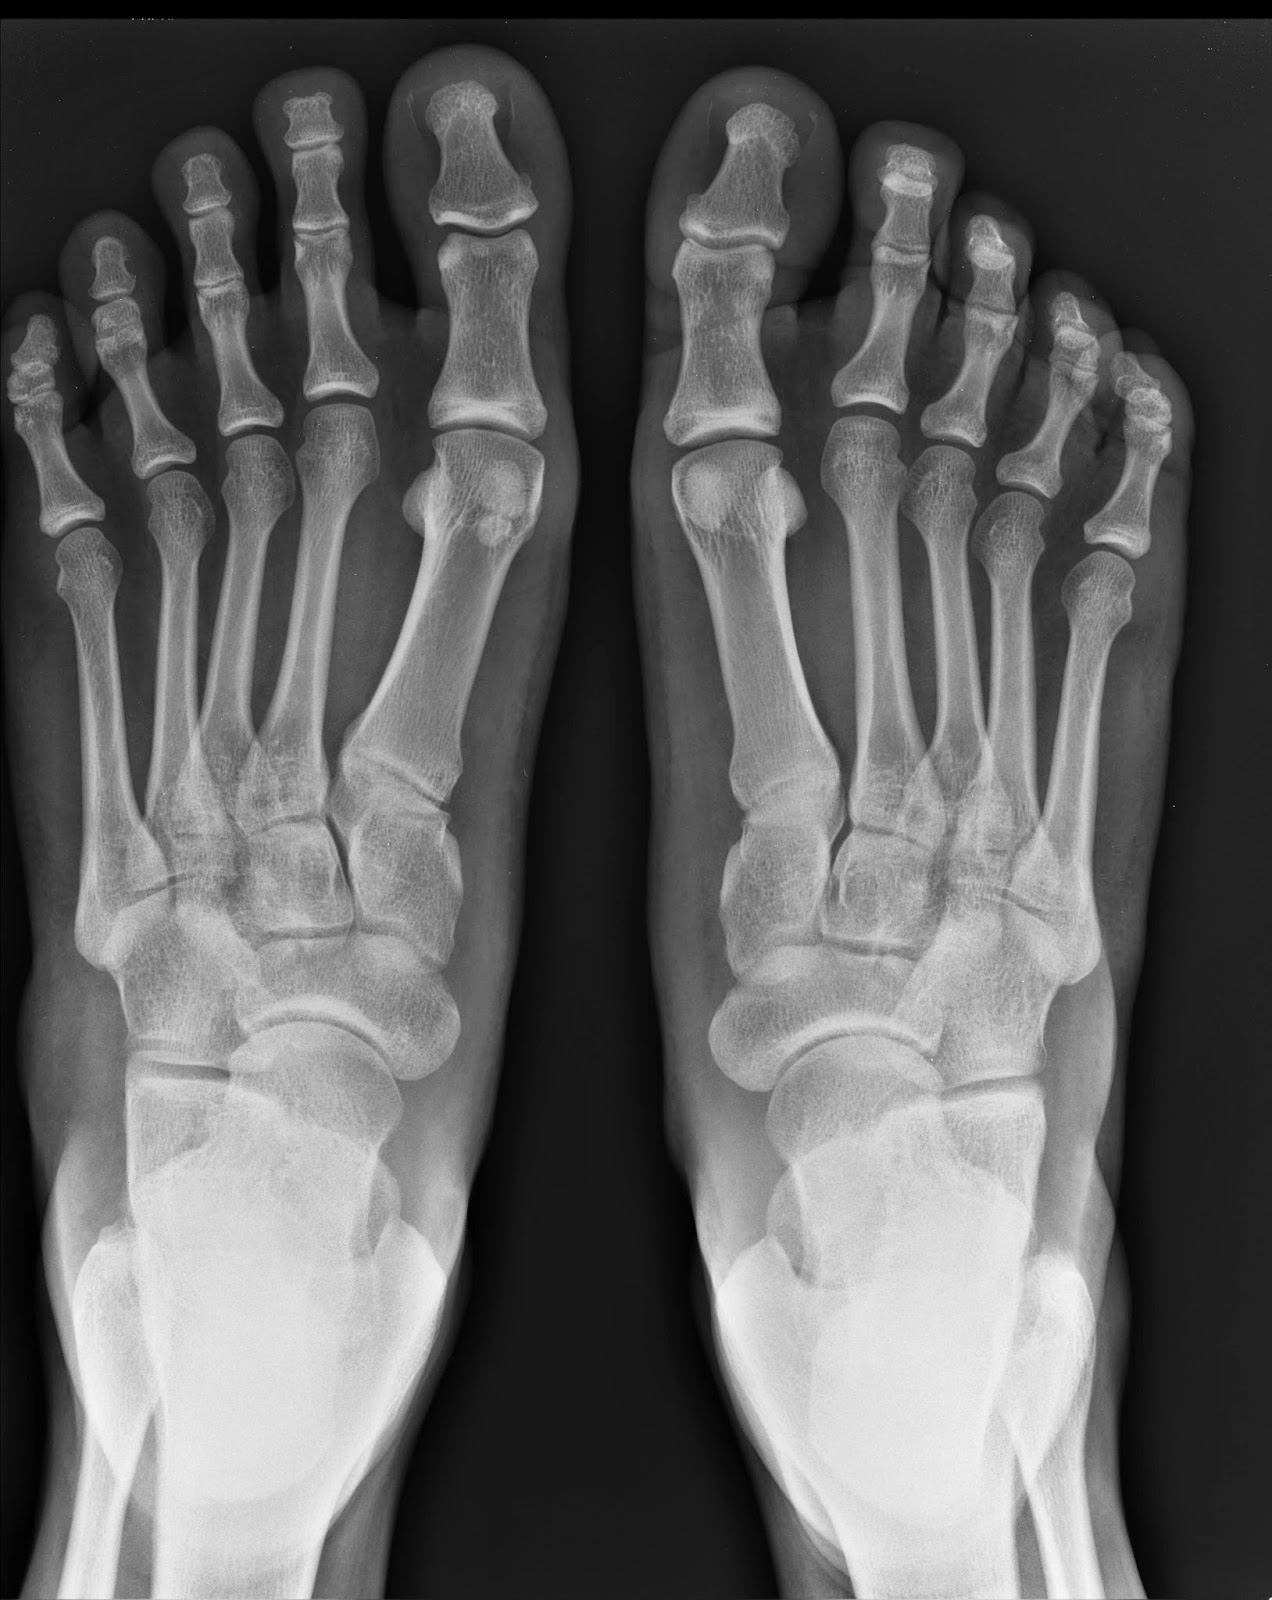

Horrifying Xray shows why you should not put your feet on car

Xray Of Feet On Dash . Doctors said a young woman in the passenger seat of a vehicle had her feet up on the. Not only did the impact shunt her legs backward, the airbag deploying caused her pelvis to become dislocated and her knees to then impact her face breaking her jaw bone. Police have shared a shocking image of a car crash victim’s injuries in an effort to stop passengers putting their feet on a car’s. As the image shows, the passenger’s right leg was dislocated from the hip in the crash, and the force of the impact was.